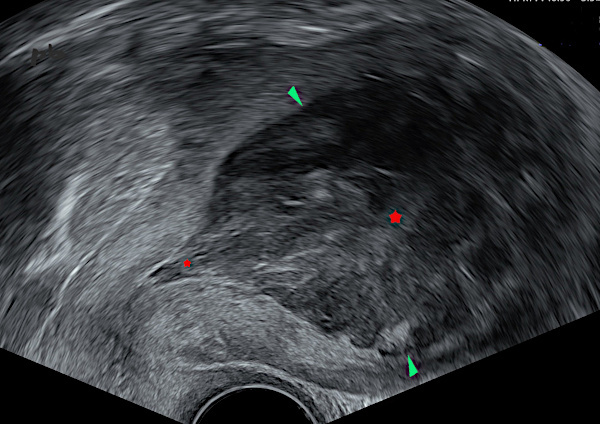

1 – Hématométrie

Coupe sagittale par voie endovaginale.

Important épaississement central (►) hypoéchogène au myomètre et hétérogène. Contours nets et réguliers.

On voit la zone s’insinuer dans le canal cervical (★), en faveur d’une localisation endocavitaire.

Mouvements particulaires en temps réel. Pas de flux en doppler couleur (non montré)

Pas d’endomètre visible.

Volumineuse hématométrie (IVG la veille). Diagnostic différentiel d’un épaississement endométrial.

1 – Hematometra

Sagittal view via endovaginal ultrasound.

Significant central hypoechoic thickening (►) within the myometrium, with heterogeneous appearance. The borders are sharp and regular. The area is seen extending into the cervical canal (★), suggesting an intracavitary location. Particular movements observed in real-time. No color Doppler flow (not shown). No visible endometrium.

Large hematometra (medical abortion the previous day). Differential diagnosis of endometrial thickening.